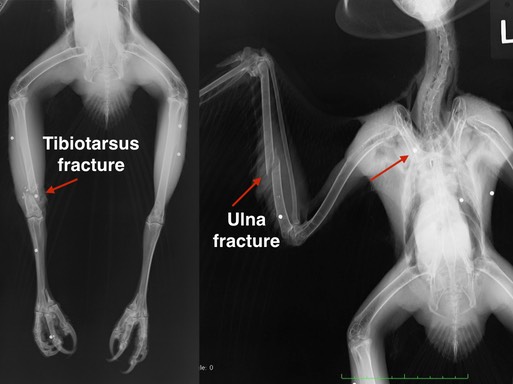

Two More Gunshot Hawks

Red-tailed Hawk 18-746 was found near Prosser, WA. She has a broken wing and a broken leg. Both fractures have been immobilized. We will have to wait and see if her right wing and right foot are functional enough for her to be released.

Sharp-shinned Hawk 18-748

Sharp-shinned Hawk 18-748, a juvenile female, was found in Boardman, OR with a badly broken right wing. Although there are no metal fragments visible in the radiograph, the fractures and wound are consistent with a gunshot injury. You can tell by the large amount of muscle mass on this hawk that she was a very successful hunter. Sadly, her wing was damaged too severely to be repaired and she was euthanized.